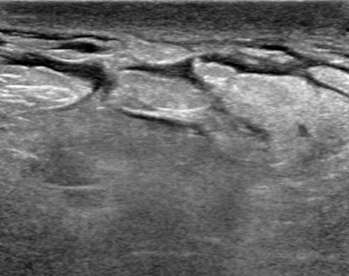

Hypoechoic mass with indistinct margins

The above ultrasound demonstrates a hypoechoic (dark) mass with indistinct margins, posterior shadowing, and distortion of the normal breast tissue. This was biopsied, revealing invasive ductal carcinoma (IDC). Both ductal carcinoma in situ (DCIS) and IDC may result in distortion.